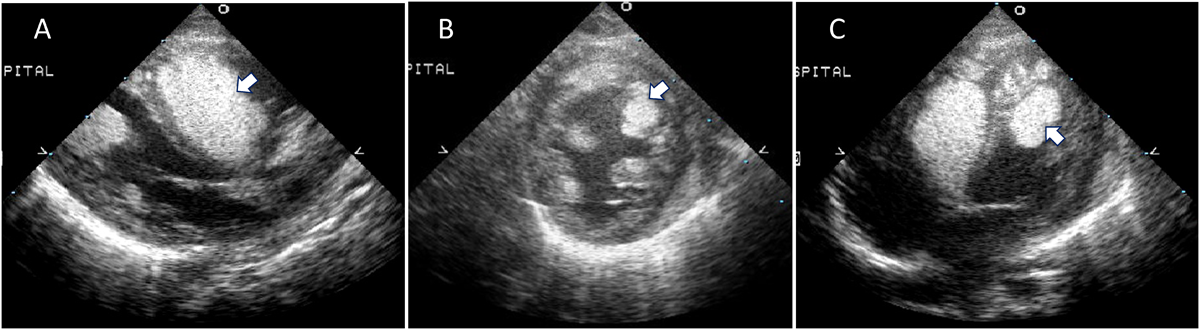

Everolimus投与後に心臓横紋筋腫が急速に退縮した結節性硬化症の1乳児例Rapid Regression of Cardiac Rhabdomyoma after Everolimus Administration in an Infant with Tuberous Sclerosis